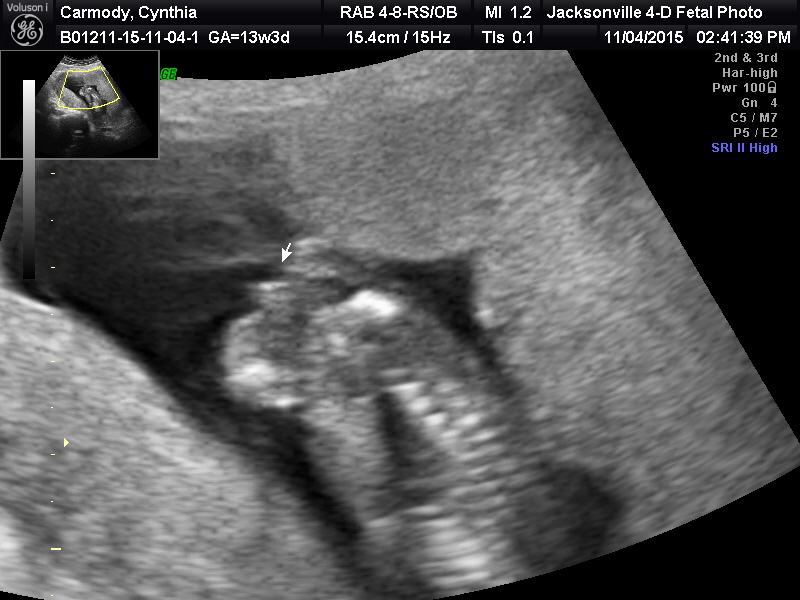

Attachment 28265Attachment 28261Attachment 28262Attachment 28263Attachment 28232Attachment 28232

I know I accidentally posted this in the wrong section. First time using this site, I didn't know how to delete it. But can you tell the gender with the pics posted?